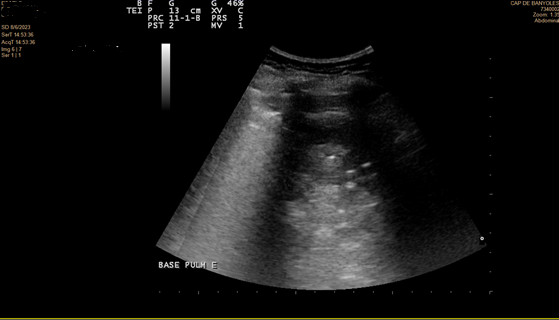

En la ecografía se objetiva irregularidad en la línea pleural, líneas B coalescentes (light beam) y un patrón de consolidación pulmonar en ambas bases pulmonares (I > D).